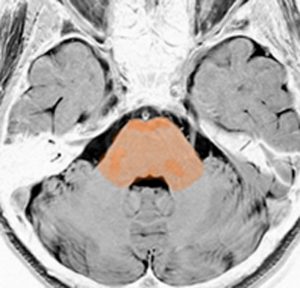

脳幹部の解剖図

- 脳の底面からしか見えないのでいろいろな角度から見ています

これは脳の中心部を縦切りにした写真です。脳幹部は上から順に,中脳 midbrain (黄色),橋 pons(オレンジ),延髄 medulla oblongata(ピンク)と呼ばれます。